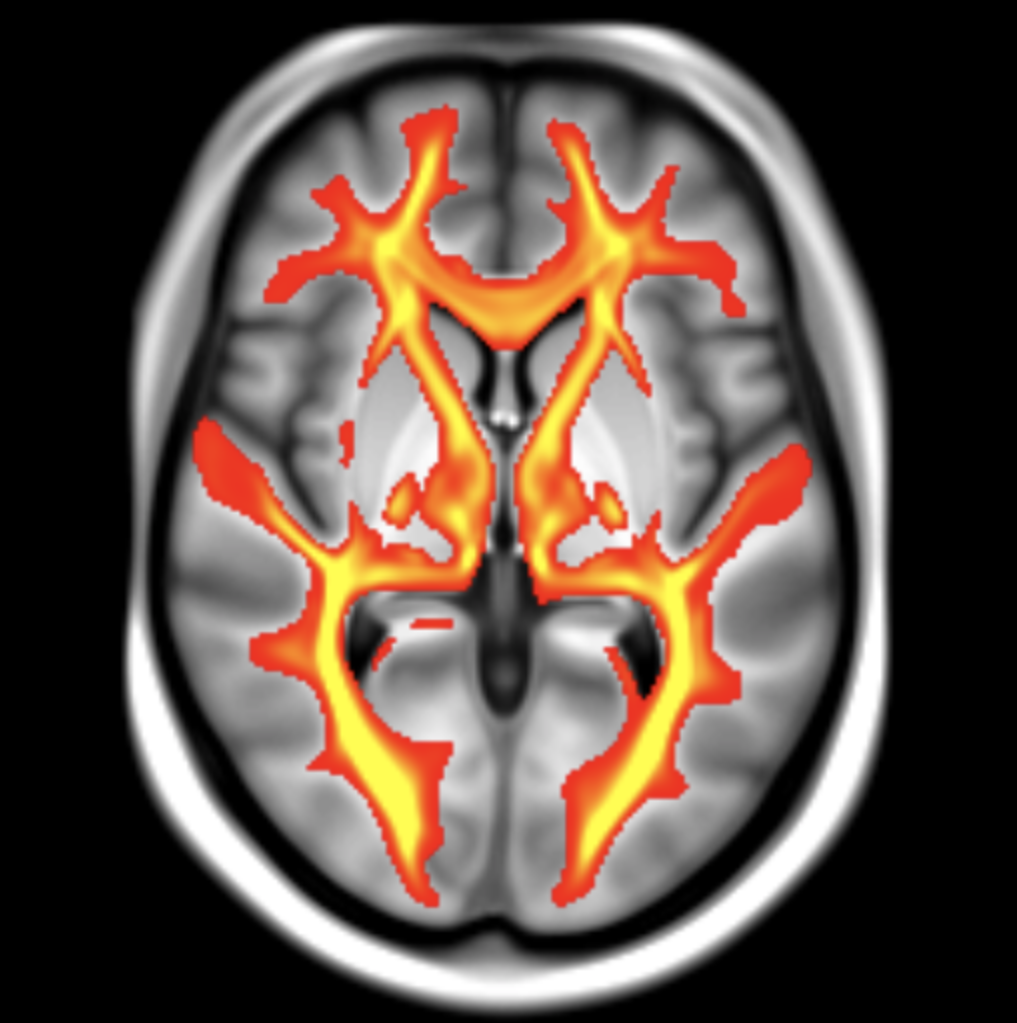

Image caption: MRI brain scan from the UK Biobank showing white matter pathways, the connections that convey information between brain regions.

These effects appear to be mediated by alterations in brain structure that were detected using new MRI brain scanning analysis techniques. The brain changes occurred in people with high blood pressure and diabetes, who were otherwise healthy individuals.

Dr. Michele Veldsman, Postdoctoral Research Scientist in Cognitive Neurology at the Department of Experimental Psychology and co-author of the study, said, ‘The MRI scans show that raised blood pressure and glucose seem to alter both the grey matter and the white matter connections in the brain.’